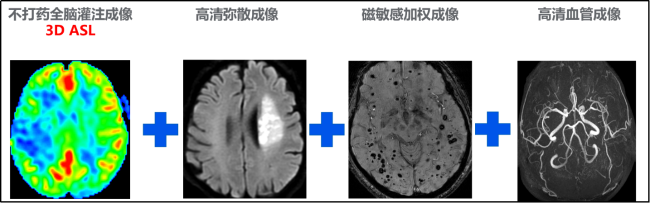

CT引进美国 GE第五代超高端大宝石能谱 CT,具有极低的放射剂量,又称为“绿色CT”,具有超快速、超精细、高清晰、后处理功能强大、高效、精准、立体的优势,确保患者得到无创、快捷、安全、准确的检查,尤其在检查心、脑及全身血管有无狭窄以及心脏塔桥、支架植入术后的复查评估有极大的优势, 对疾病能做出精准诊断,对恶性肿瘤能做出精准的分级及分期,能对恶性肿瘤的疗效做出精准的评估,能对肺部小结节的风险进行精准的评估,能对复杂骨折做出精准诊断,能对泌尿系结石成份进行分析,利用去金属伪影的技术,能精准判定内固定器的情况及手术效果,是亚健康人群体检与患者检诊的最佳选择。另外我院又配置联影530及车载移动CT各一台,满足了不同层次患者的需求。 CT 室咨询电话:2739333